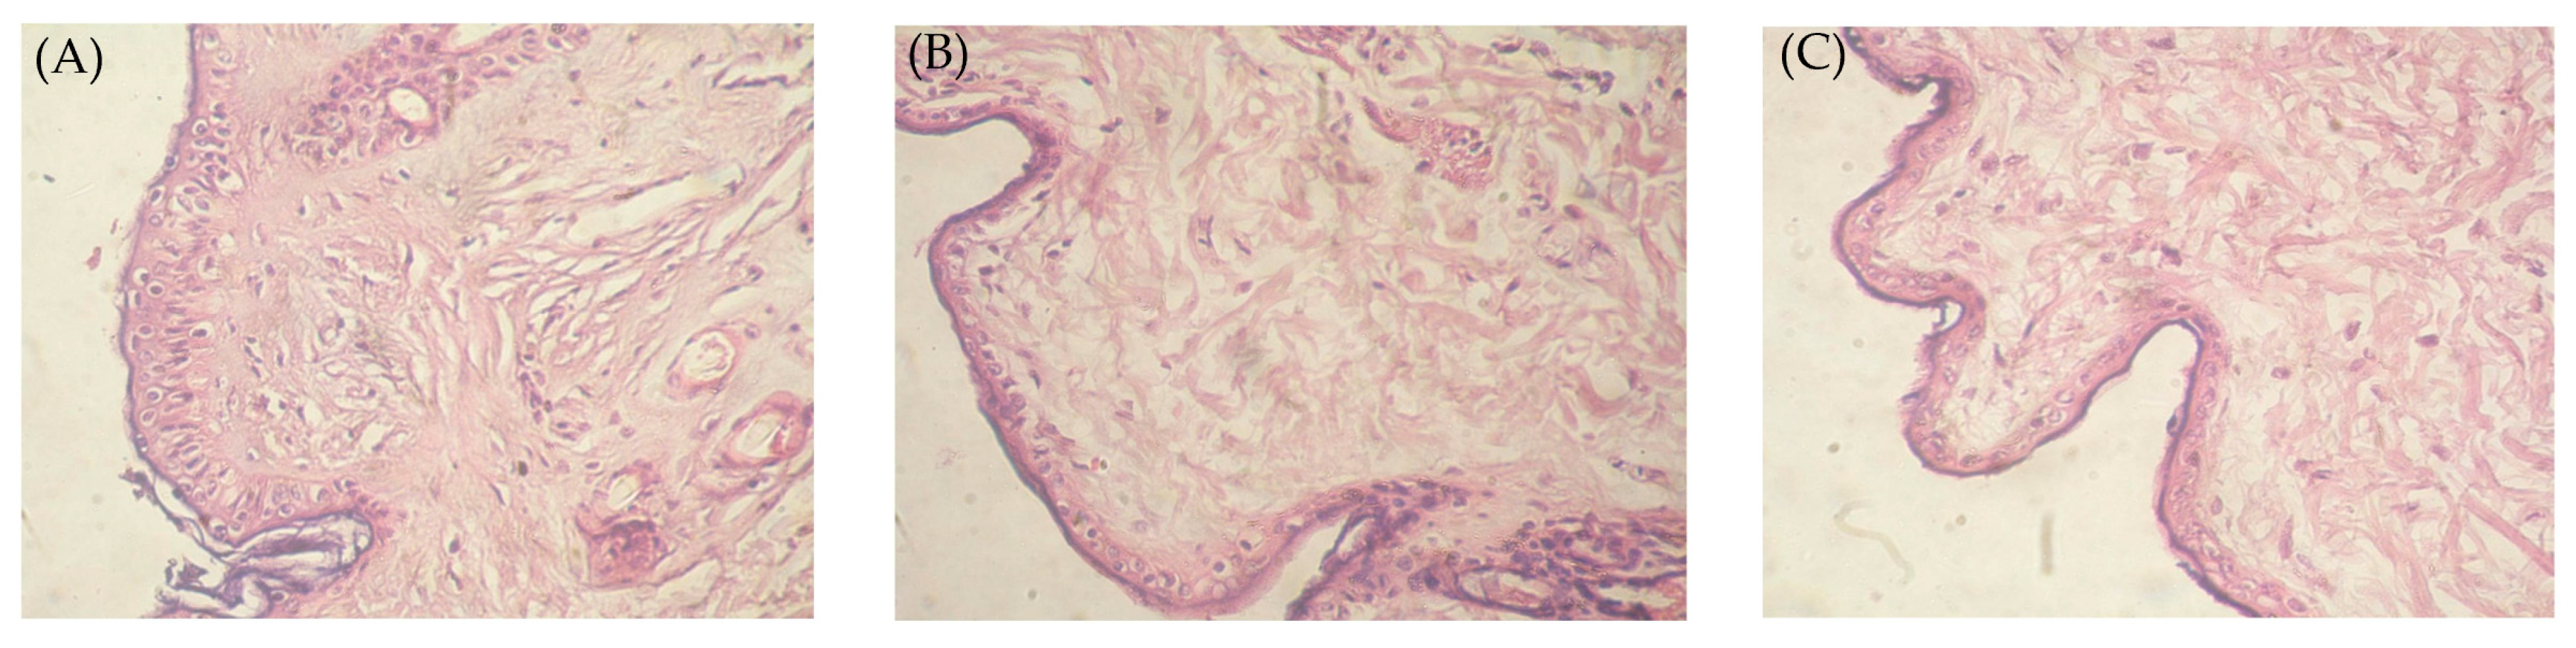

2.12. Histopathological Study of the Optimized Nanoemulgel

4.11. Histopathological Study of the Optimized Nanoemulgel